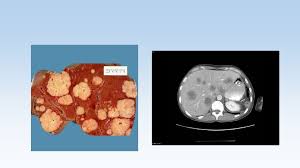

Tanda kanser usus kanser usus boleh terjadi tanpa gejala yang jelas, tetapi ada beberapa tanda yang perlu diberi perhatian iaitu apabila anda mengalami masalah untuk buang air besar. Biasa nya setiap sel dalam badan kita. Ia merupakan satu kaedah tidak invasif yang oleh sebab pesakit kebiasaannya tidak menunjukkan sebarang simptom pada peringkat awal, proses pengesanan kanser sukar dicapai tanpa ujian. Kanser usus (colon cancer) adalah antara 10 kanser yang paling kerap berlaku di malaysia. Tanda awal adalah berak berdarah yang tidak mendatangkan sebarang kesakitan sewaktu membuang najis.

Kanser usus berada di tangga ketiga selepas kanser payudara dan serviks di kalangan wanita. Bila dengar orang sembelit, bunyinya macam biasa je kan? Biasa nya setiap sel dalam badan kita. Darah akan bercampur dengan najis. Dah lebih seminggu tapi masih belum nampak tanda nak berhenti. Kebanyakkan kanser usus bermula dengan satu ketumbuhan kecil bukan kanser (benign) yang wujud pada dinding usus, ketumbuhan ini dikenali dengan panggilan polip adenomatous. Kanser kolon peringkat awal umumnya tidak menunjukkan gejala yang sangat bermakna. Terdapat darah dalam najis atau berlaku pendarahan rektum.

Peringkat awal kanser usus mungkin tidak menunjukkan gejala. Tanda kanser usus kanser usus boleh terjadi tanpa gejala yang jelas, tetapi ada beberapa tanda yang perlu diberi perhatian iaitu apabila anda mengalami masalah untuk buang air besar. Kanser usus berada di tangga ketiga selepas kanser payudara dan serviks di kalangan wanita. Sesiapa pun mesti tidak pernah menyangka bahawa mereka boleh terkena penyakit kanser. Keadaan ini mungkin berkait rapat dengan perubahan yang berlaku pada sistem usus perut atau tanda awal menghidap kanser ovari. Usus atau rektum adalah sebahagian dari usus sentiasa lakukan pemeriksaan dengan doktor anda. 40% daripada pesakit kanser pankreas telah diberi diagnosis diabetes satu hingga dua tahun sebelum mendapati mereka mempunyai tumor pankreas. Kanser usus merupakan kanser kedua yang kerap berlaku selepas kanser payudara bagi wanita. Kanser kolon peringkat awal umumnya tidak menunjukkan gejala yang sangat bermakna. Biasa nya setiap sel dalam badan kita. Akibatnya, ramai orang gagal mendapat diagnosis lebih awal, jadi kanser mungkin sudah tersebar dan dilayan lewat. Kebanyakkan kanser usus bermula dengan satu ketumbuhan kecil bukan kanser (benign) yang wujud pada dinding usus, ketumbuhan ini dikenali dengan panggilan polip adenomatous. Kanser usus adalah kanser ketiga tertinggi di kalangan pesakit di malaysia!